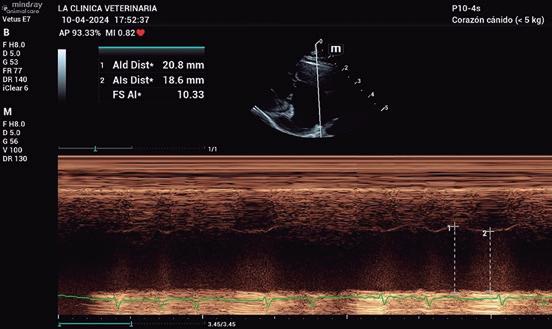

Estudio ecocardiográfico

• Modo B: en la proyección paraesternal derecha eje largo, se observó un jet de regurgitación mitral con dirección posterior y SAM (figura 3). En el eje corto derecho a la altura de la base cardiaca se observó un ratio atrio izquierdo/aorta (AI/Ao) de 1,92 (>1,6 se considera dilatación AI) (figura 4). Además, se observó hipertrofia de la pared del septo interventricular (SIV) de 7,6 mm y la pared libre del ventrículo izquierdo (PLVI) la 8,4 mm (hipertrofia >6 mm) (figura 5).

• Modo M: en paraesternal derecho eje corto a nivel de músculos papilares se observó un aumento del grosor del SIV en sístole (SIVs) de 7,8 mm (hipertrofia >6 mm), así como una hipertrofia de los músculos papilares (figura 6). • Modo Doppler: en la proyección paraesternal izquierda apical cuatro cámaras se midieron los flujos mitral (onda E 0,89 m/s y onda A 0,66 m/s) y subaórtico (4,56 m/s) (figura 7) ambos turbulentos, pero con velocidades dentro de rango. Presencia de ODTSVI. El flujo dentro de la aurícula izquierda estaba ligeramente disminuido (0,23 m/s, rango <0.25 m/s), aunque sin smoke

Para el diagnóstico de fenotipo hipertrófico, la gold estándar es la ecocardiografía. Aunque no hay una medida mundialmente aceptada para un valor normal o anormal de grosor de la pared, un aumento focal o difuso por encima de 6 mm (Fuentes et al. 2020) confirma el diagnóstico. Un AI/ Ao >1,6, justifica la presencia de ICC. En nuestro caso, el diagnóstico de fenotipo hipertrófico, se sustenta por el aumento del grosor de la pared del VI (7,6 mm en modo B y 7,8 mm en modo M) y la ICC, por el del AI/Ao (1,92).